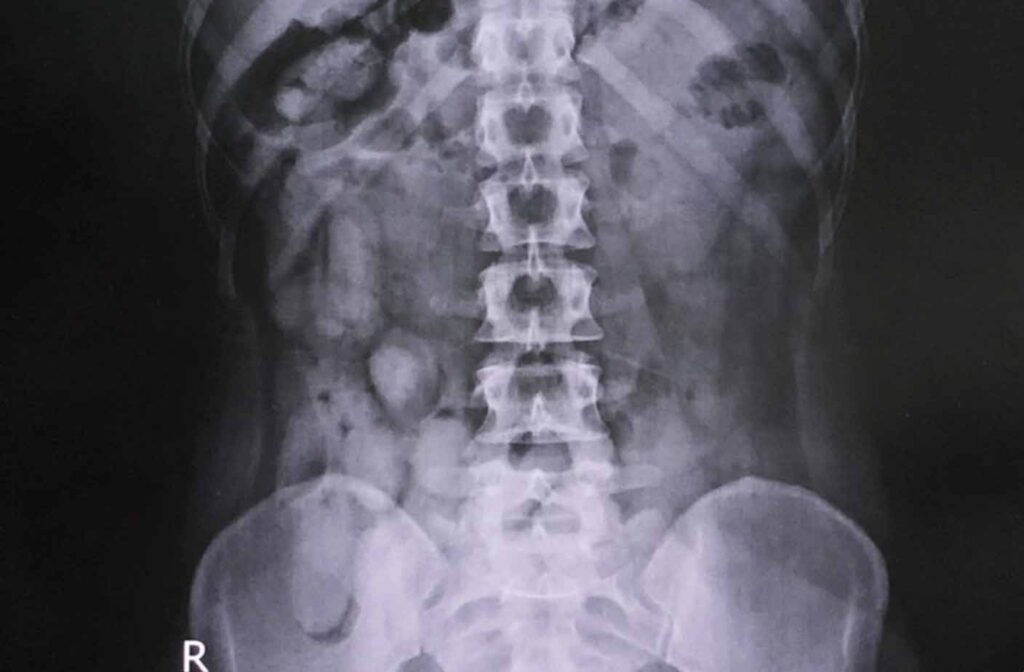

צילום רנטגן

שלוש הנשים הועברו לבית החולים טאלנג על האי, שם בוצע צילום רנטגן של אזור החזה והבטן.

ממצאי הצילום העלו כמות גדולה של קפסולות קוקאין ארוזות בבטנן ובאיבר המין של אחת מהן.

סך הכל הוצאו מגופן קפסולות מלאות קוקאין במשקל כולל 2,857 גרם (כ3 קילוגרם) בשווי העולה על 10 מיליון שקלים (כביליון באהט).